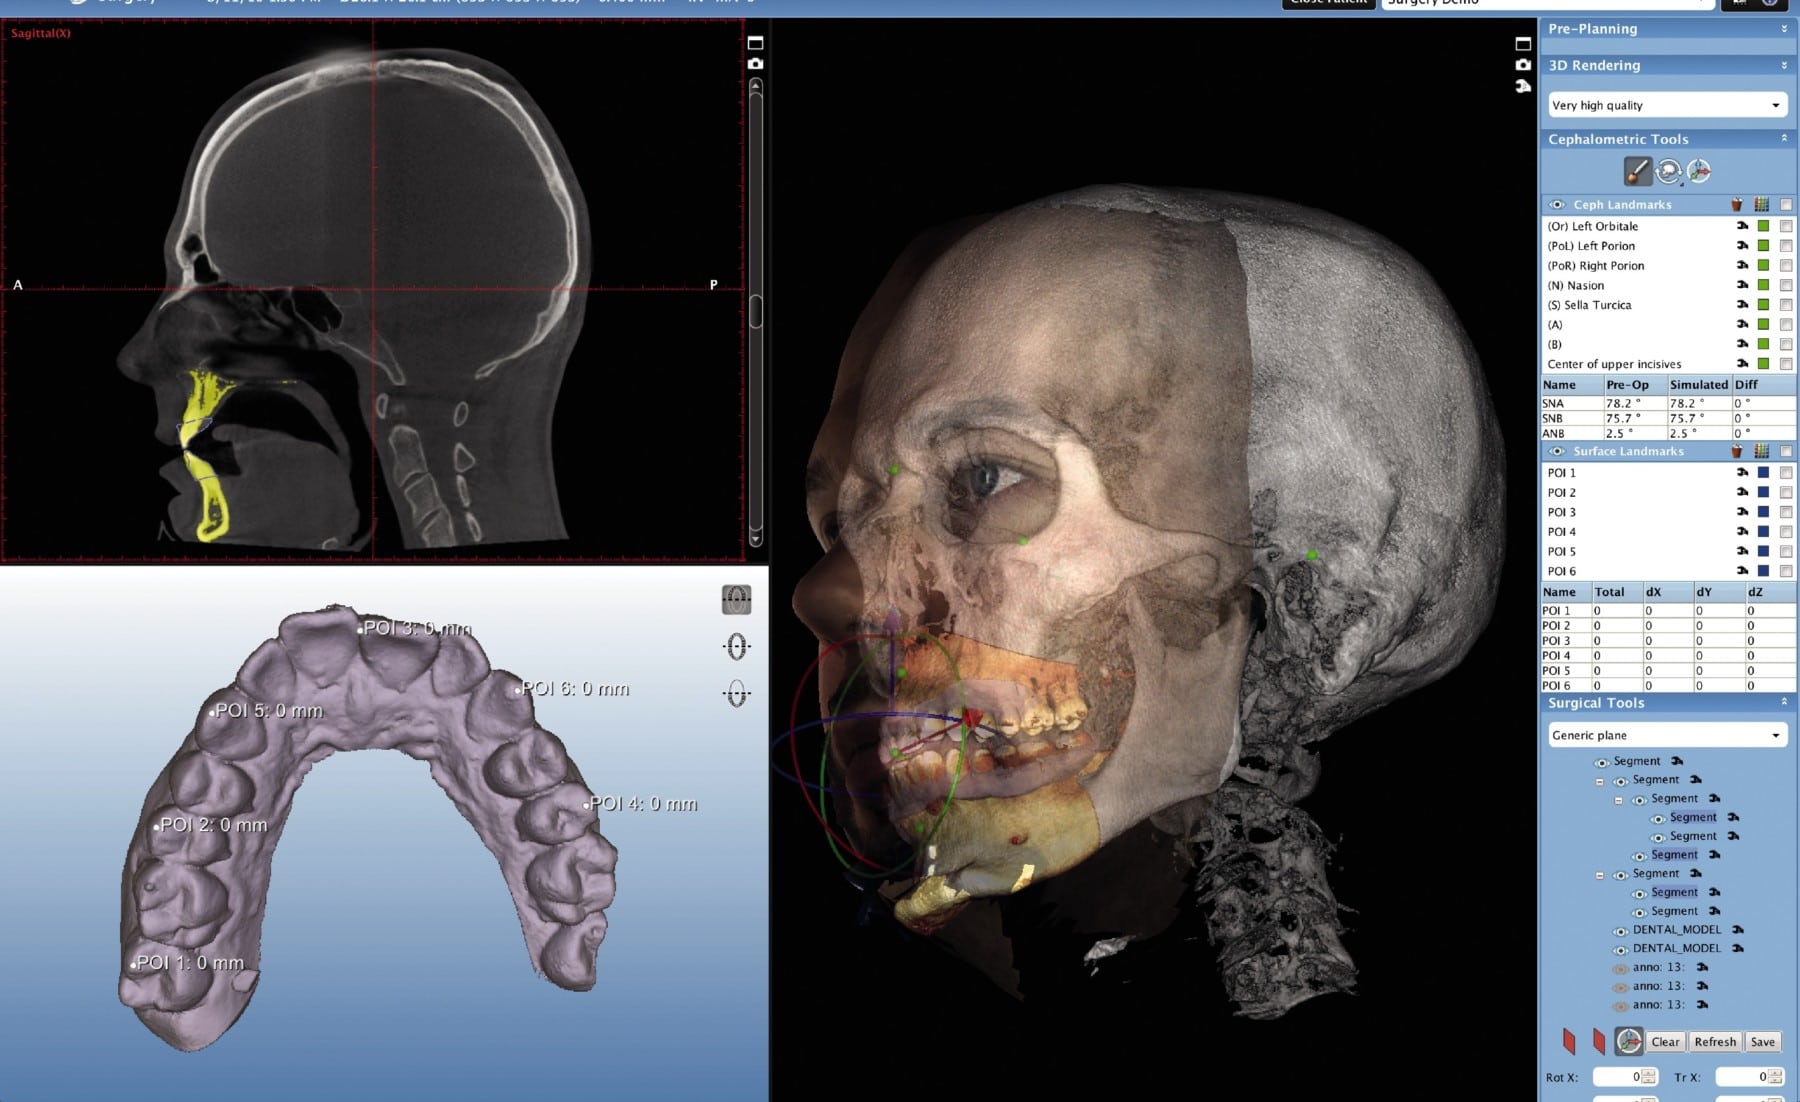

| Automated Anatomy Segmentation | 3D nnU-Net trained on 50k CBCT volumes with manual ground truth (Dice coefficient >0.94) | Reduces landmark error from 0.32mm to 0.11mm RMS | Cuts planning time by 6.2 minutes/case (implant surgery) |